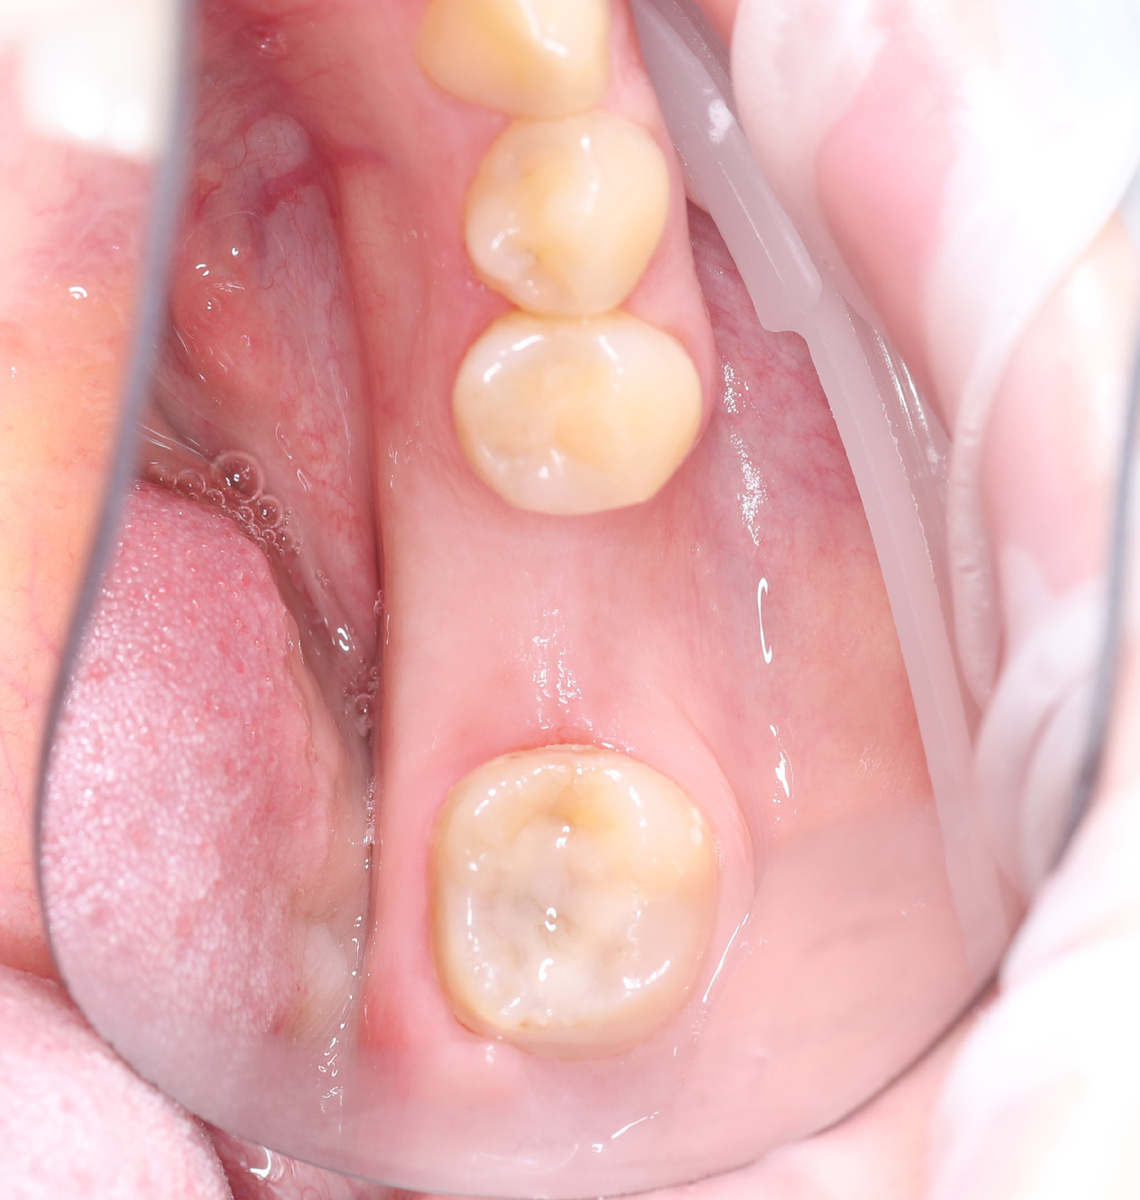

Ситуация «до»:

Утерян объём десны. Его мы восстановили за счёт пересадки десневого трансплантата из области бугра верхней челюсти.